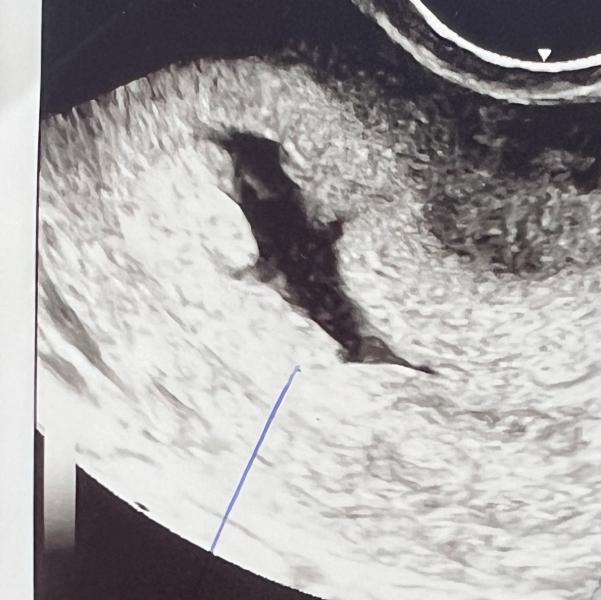

Подскажите пожалуйста, была ли у кого-то жидкость в матке? Врачи не смогли сказать что это. Я вся на нервах(((

Мне врач как сказала «30 лет практики, первый раз такое вижу», кандидат медицинских наук. Я вообще чуть в обморок там не упала